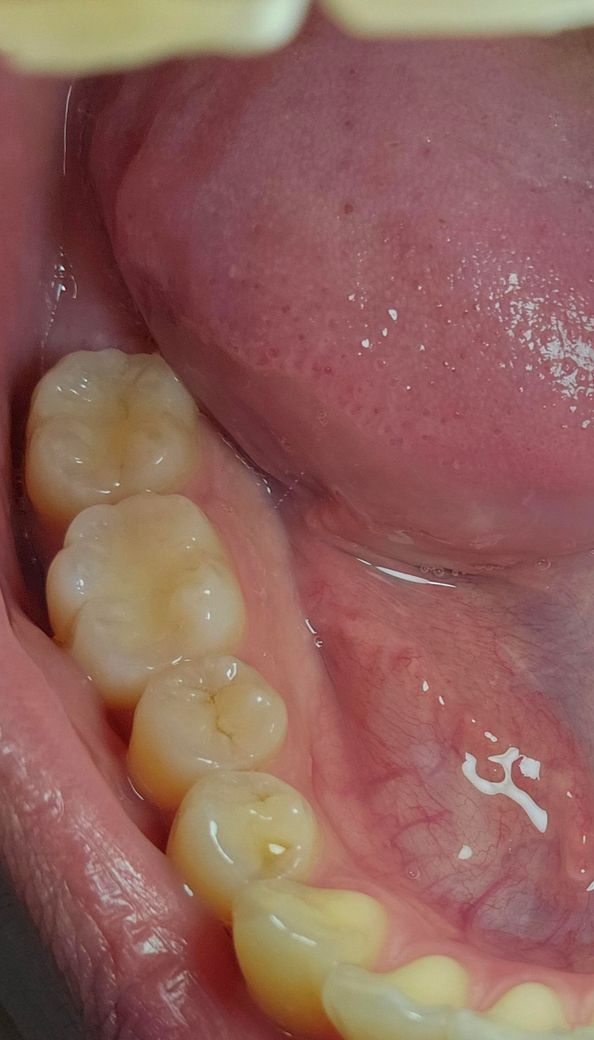

이정도로 진행된 충치는 치과에서 치료하는 편인가요?

치실을 쓰다가 어금니에 거뭇거뭇한 점이 보였는데 착색이거니 하고 넘겼는데

날이 갈수록 그 검은 게 점점 확대되는 것 같은 기분이 듭니다.

지금은 이 정도인데 치과에서 저 정도 충치는 치료하자고 진단하나요?

안쪽에서 세번째 어금니요!

• 1번 째 사진

저정도 충치라면 간단한 충치라서 충치를 제거하고 레진으로 치료를 하시는게 좋을것같습니다.

현재 보여주신 사진에서는 큰 문제가 보이지 않습니다. 다만 충치 및 치아 질환을 판단하는데 있어서는 다각도적인 평가가 필요합니다. 따라서 사랑니를 위해 치과를 방문할 때 해당 부분에 대한 검사도 같이 해보시길 바랍니다.

지금 상태에서는 치료를 하기보다는 지켜볼 것 같지만 크기가 더 커진다면 치료하셔도 됩니다.

검은 점이 어금니에 생겼다면 충치일 가능성이 있습니다. 충치가 진행될수록 색깔이 검거나 갈색으로 변하고, 그 부위가 점차 확대되는 경향이 있습니다. 검은 점이 점차 확대되는 것 같다고 느끼는 경우 충치가 진행되고 있을 가능성이 높기에 가급적 빨리 치과에 방문하여 상태를 확인하고 치료를 받길 권합니다.

두번째 작은 어금니 초기 충치의 양상으로 보입니다.

엑스레이를 찍어봐야 정확히 판단 가능하나 그리 깊은충치는 아닐 것 같습니다.